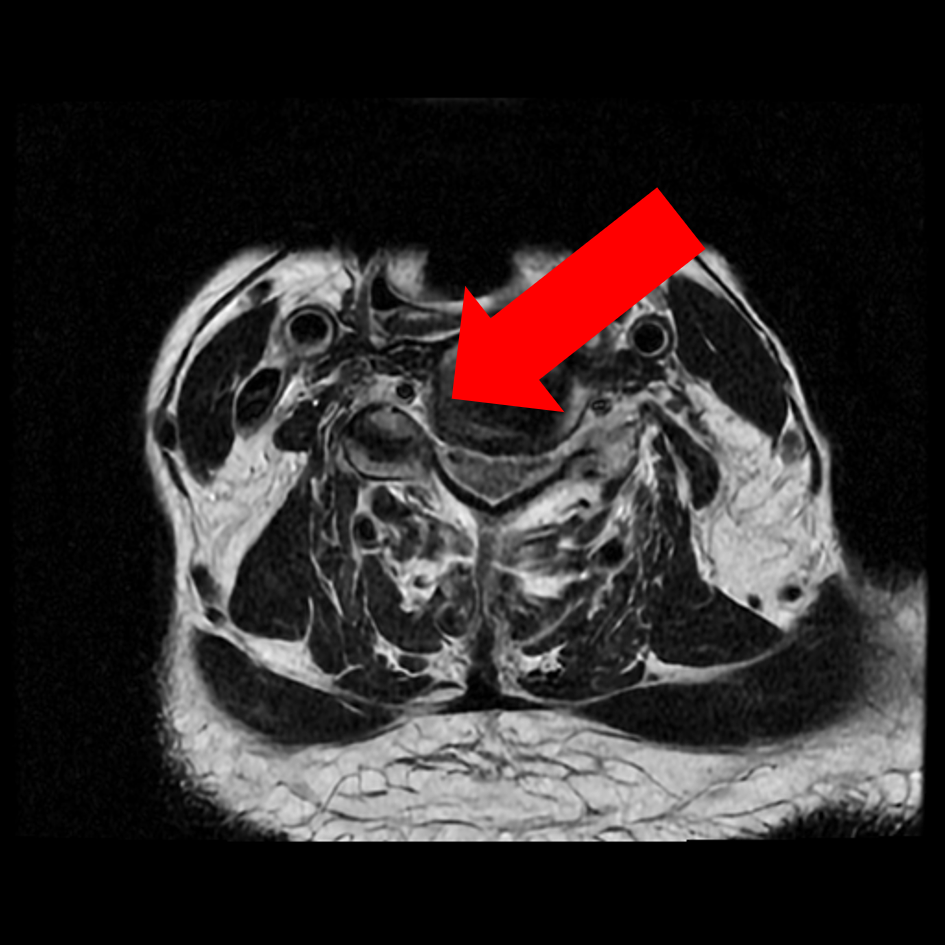

圖二、【術前評估】第五、第六頸椎椎間盤突出往後擠壓到脊髓腔(如左圖箭頭)、椎間盤突出往後偏右擠壓到第六條神經(如右圖箭頭)。

圖三、【術前評估】第六第七頸椎間盤突出往後擠壓到脊髓腔(如左圖箭頭)、同時顯示椎間盤突出往後偏右已擠壓到第七條神經(如右圖箭頭)。